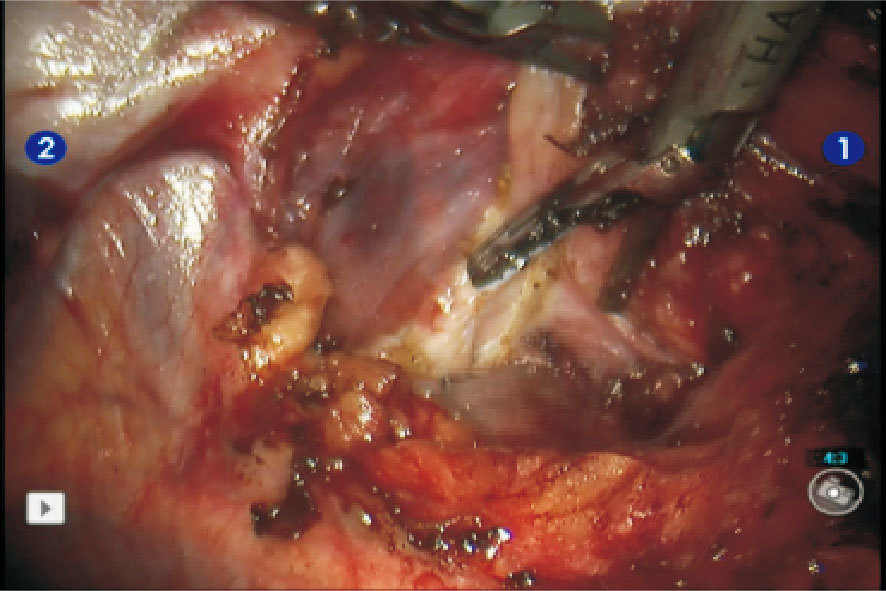

術者于控制臺前、三維視野下開始手術操作。在右膈神經前方,心包前上方近返折處,提起瘤體下極表面的縱隔胸膜,沿膈神經走向在其前方銳性打開,由下向上進行解剖。隨后向胸骨方向提起瘤體,充分游離瘤體右側邊界及背側,使之和膈神經完全脫離(圖 4)。于胸骨后相同走向打開縱隔胸膜,游離腫瘤腹側,注意保護胸廓內動脈,防止損傷。牽拉瘤體下極,鈍性加銳性解剖游離至對側縱隔胸膜,鈍性推開纖薄的縱隔胸膜,注意尋找保護對側膈神經,沿心包和升主動脈表面自下向上游離,使腫瘤左側邊界和對側縱隔胸膜完全脫離。充分游離了下極、左右側和背腹側后,向右胸腔內牽拉腫瘤,充分暴露腫瘤上極。分離尋找出右無名靜脈和上腔靜脈交匯處,沿其表面向左無名靜脈遠端進行解剖游離。沿途發自左無名靜脈的腫瘤營養支血管(胸腺靜脈),以超聲刀直接夾閉凝斷(圖 5)。較粗的營養支血管,可以鈦夾或Hem-o-lok夾關閉后凝斷。離斷上極后,完成腫瘤切除。

注:胸腺靜脈已凝斷